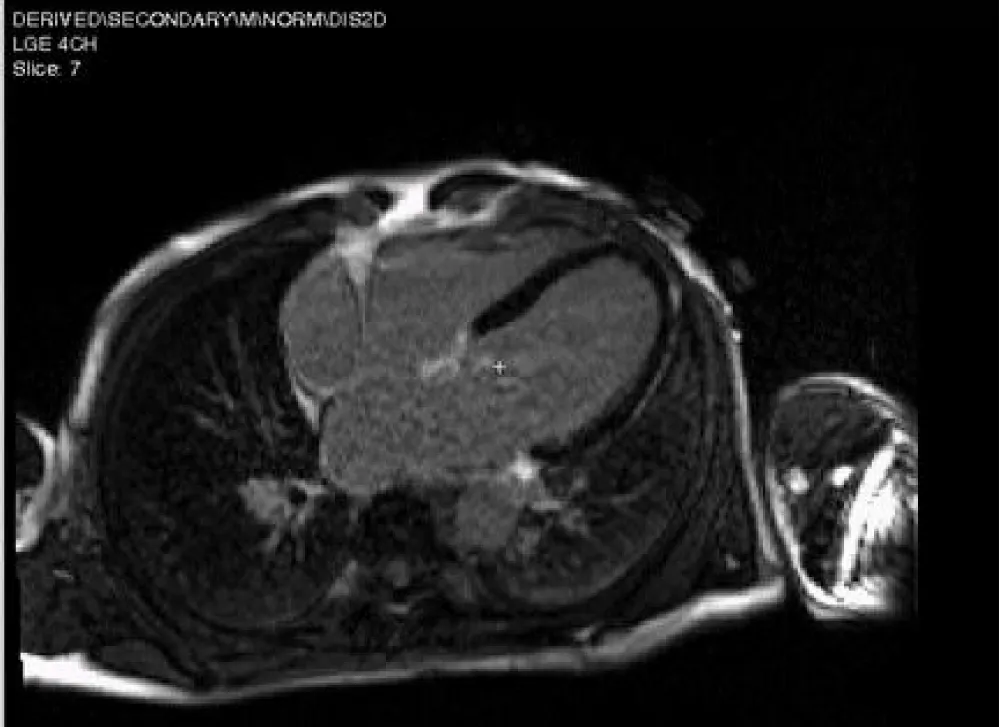

Case 1 (myxomatous mitral valve disease with flail posterior mitral leaflet)

62 years old male, not known to be diabetic or hypertensive or a smoker presented with dyspnea on minimal exertion (NYHA class III). 2D echocardiography revealed flail posterior mitral leaflet with severe mitral regurgitation resulting in mild dilatation of LV, mildly impaired systolic function, EF = 56% and mildly impaired GLS = -17.2%. 3D echo revealed the same data with EF = 55%, GLS = -19.4%. CMR showed mildly dilated LV with mildly impaired LV systolic function, EF = 57%, GLS = -17.7%. No fibrosis was detected at LGE (Figures 1-5).

Figure 4: CMR-LGE 4 chamber view revealed no fibrosis.